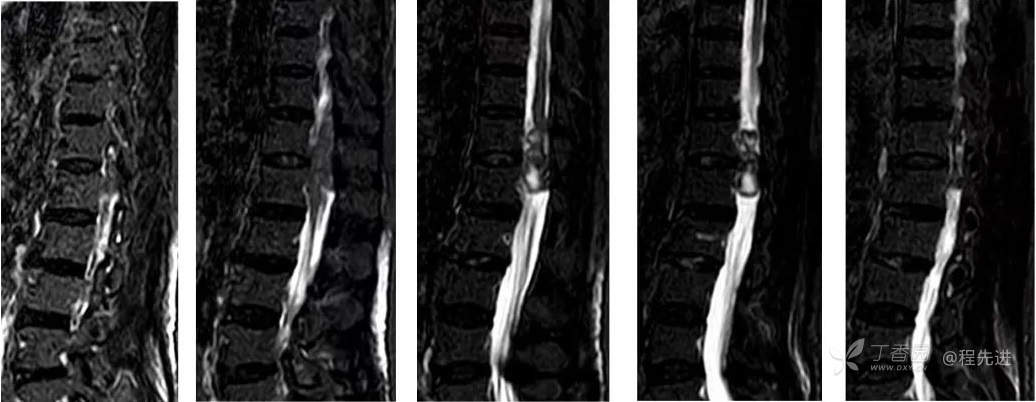

MR: